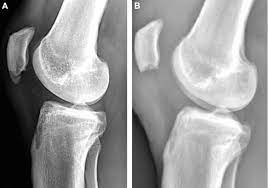

Sinding Larsen Johansson Syndrome A Radiograph Of A 10 Year Old Boy Download Scientific Diagram